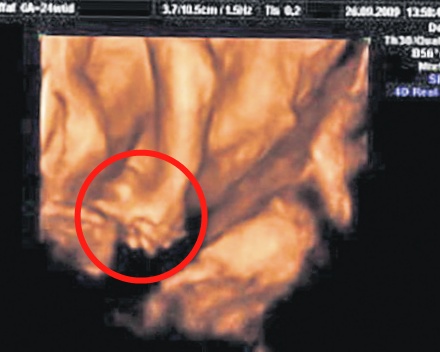

| Micuţii continuă să se ţină de mână aşa cum obişnuiau să facă şi în burtica mamei, după cum arată o ecografie (foto dreapta) realizată la 24 de săptămâni | |

Deşi Hassan şi Hussein Benhaffaf au fost separaţi în urma unei intervenţii chirurgicale, micuţii par că vor să înfrunte totul împreună, fiind de nedespărţit. Cel puţin asta demonstrează nişte instantanee incredibile, realizate de jurnaliştii de la tabloidul News of the World, cu micuţii care se ţin de mânuţe, exact cum au fost surprinşi şi în ecografia făcută pe când erau în burtica mamei lor şi aveau doar 24 de săptămâni.